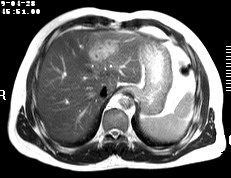

标题: CT19720:肝右叶血管瘤。肝左叶内侧段病灶考虑什么? [打印本页]

标题: CT19720:肝右叶血管瘤。肝左叶内侧段病灶考虑什么?

男,48岁,肝区不适月余,伴隐痛。

支持右叶血管瘤,左叶病灶考虑肝腺瘤。

1)不排除肝左叶肝癌。2)肝右叶血管瘤。

肝左叶炎性病变,肝癌待排。2)肝右叶血管瘤。

1.肝右叶血管瘤;2.肝左叶炎性假瘤?肝癌?建议穿刺活检.

右叶病灶典型,左叶病变慢性炎块

1、肝右叶血管瘤(典型)。

2、肝左叶病灶,强化不明显,疑炎性假瘤,建议结合临床并密切随访。

1、肝左叶炎性病变,肝癌待排。

2、肝右叶血管瘤。

肝左叶脓肿,肝癌待排。2)肝右叶血管瘤